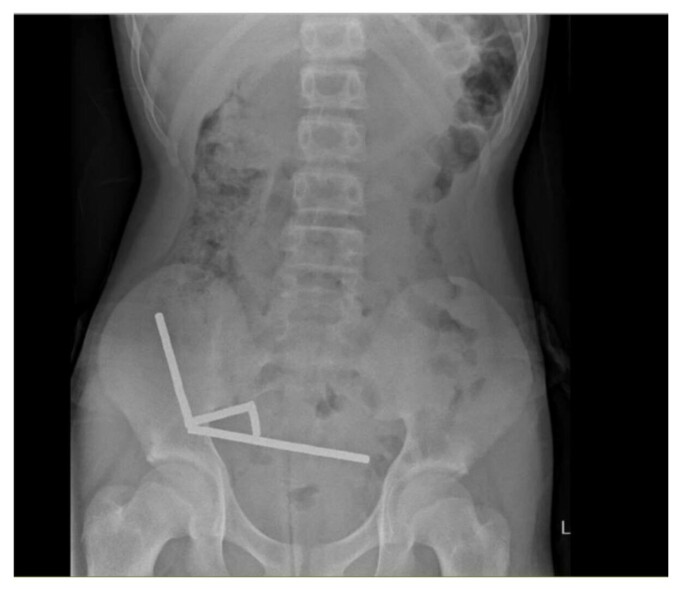

Scanările au arătat că magneții se adunaseră în patru lanțuri în partea dreaptă inferioară a abdomenului, lipind între ele diferite secțiuni ale intestinului cu forța lor magnetică, se arată în raport, care notează că unele imagini au fost distorsionate din cauza magneților. Medicii au decis să efectueze o intervenție chirurgicală exploratorie.